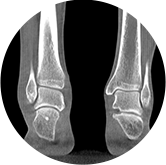

足踝